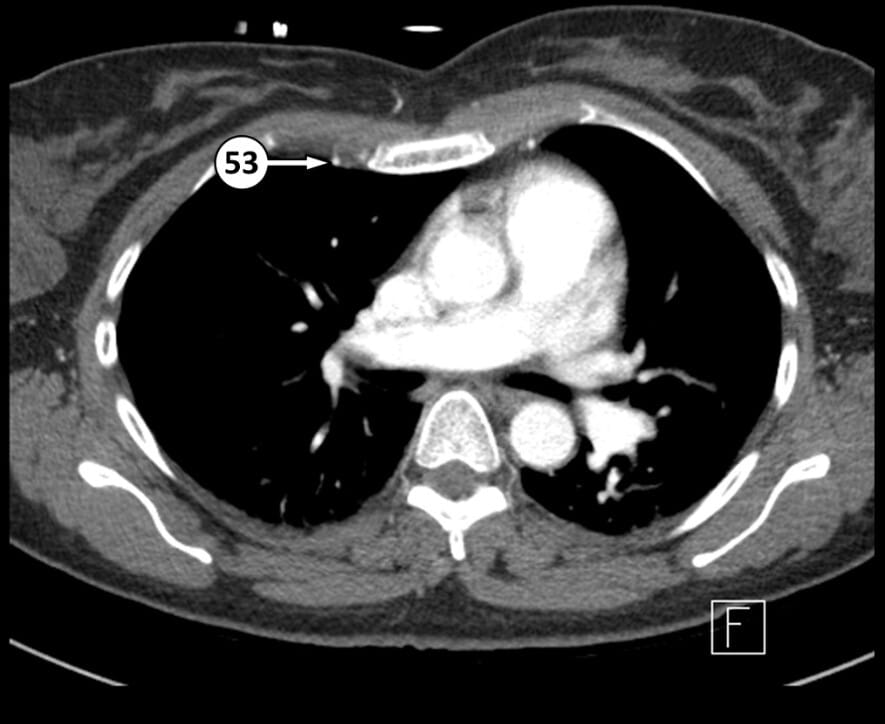

53. internal thoracic artery